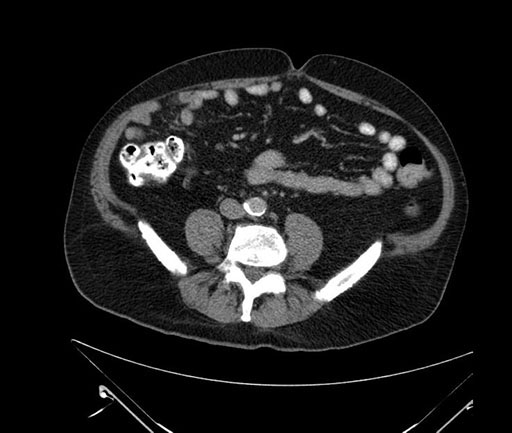

Imaging Analysis

Look through the patient's CT scan to identify any areas of concern for the necessary procedure.

Based on your CT findings, which issue(s) would give reason for "planned slowing down moment(s)" in this case?